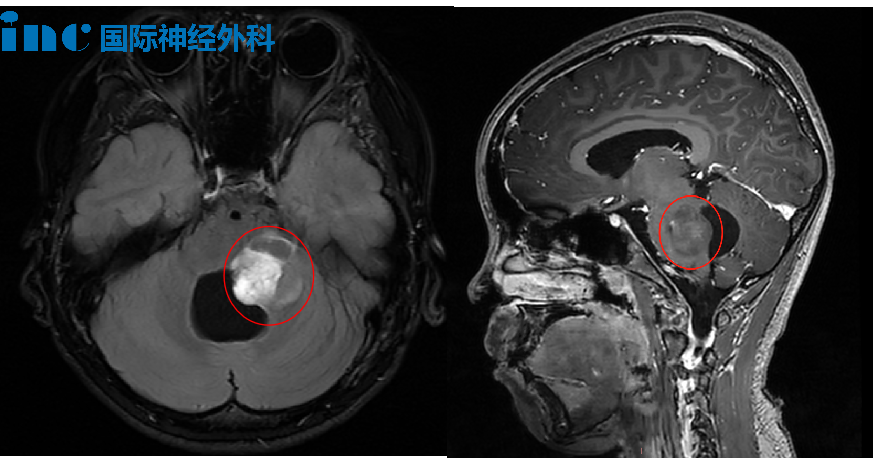

9岁女童茜茜自6岁起反复出现头痛、头晕症状,初期家长未能充分重视。8岁时因感冒就医,经神经外科检查及MRI扫描,确诊为脑干胶质瘤。得知诊断结果后,家属情绪受到严重冲击。医疗团队告知该疾病需重点考虑生存期问题。

2022年10月24日确诊后,患儿于当月底入住当地医院,完成增强MRI等系列检查后立即接受手术治疗。首次手术后患儿状态较差,直接转入ICU监护,术后病理诊断为毛细胞星形细胞瘤。术后出现面瘫和眼睑下垂等神经功能缺损症状,但保留了独立行走能力。